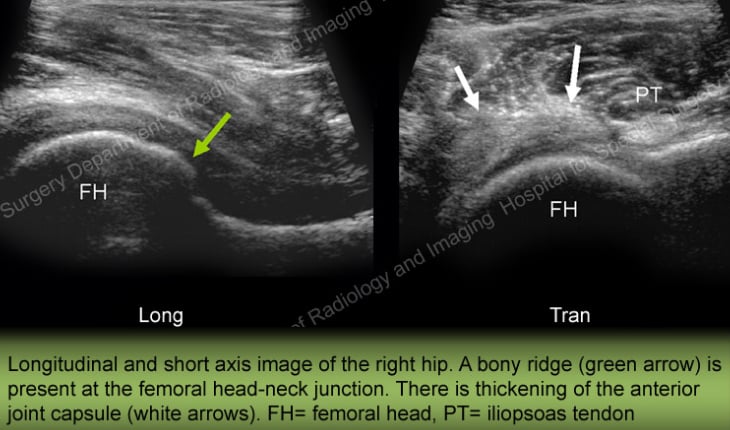

Ultrasound

Ultrasound is extremely sensitive for identifying synovial cysts that sometimes form in joints which have osteoarthritis. It is also excellent for evaluating the ligaments and tendons around the joint.